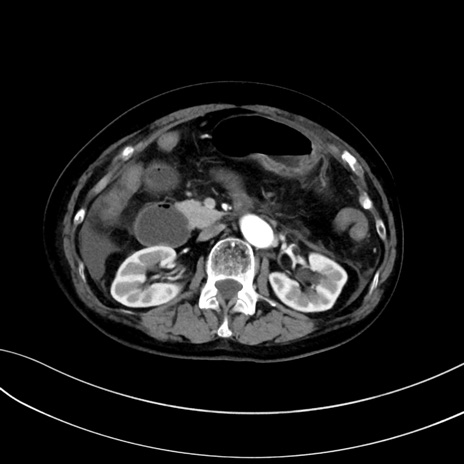

症例13 CT(横断像)1日半後